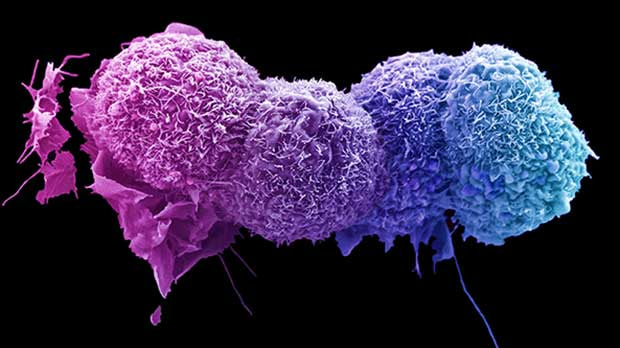

Câncer:

1° Batalha Câncer: Progestágeno VS Progesterona

Progestágeno sintético –

TRIPLICA o risco do desenvolvimento de câncer de mama quando associado a o estradiol sintético, pode ocorrer devido a:

Diminuição de:

Apoptose (morte das células), aumentando assim a mitose (divisão celular) favorecendo a proliferação de células mamárias cancerígenas induzidas por estrogênio.

Aumento de:

- Up-regulation da ciclina D1

Conversão dos estrógenos endógenos fracos nos mais potentes, aumentando do metabólito estrogênico genotóxico 16 hidroxi estrona.

Expressão dos genes intramamários proliferativos como o ki67 e ciclina B1

Alteração do equilíbrio entre os receptores de progesterona do tipo A e B

Progesterona bioidêntica

É associado com diminuição do risco de câncer de mama

Baixa progesterona endógena pode aumentar por exemplo o risco do desenvolvimento câncer mamário em até 5.4 x no período pré-menopausa.

Ocorrem 10x mais mortes em mulheres com baixa progesterona.

Sua ação anti-cancerígena ocorre devido à:

Diminuição de:

Estímulo das células epiteliais mamárias, induzidas por estrogênio

Atividade dos receptores estrogênicos do tipo 1 na mama

Atividade mitótica das células mamárias, diminuindo sua proliferação em até 400%

Ciclina D1

Progressão da célula cancerígena na fase G1

Aumento de:

Apoptose de células de câncer mamárion

Ação antiestrogênica significativa no tecido mamárion

Conversão intracelular de estrógenos potentes para suas versões mais fracas

2° Batalha Câncer: Estrogênio Bioidêntico VS Sintético

Estrógeno sintético:

Liga-se seletivamente aos receptores Alfa estrogênicos (promove o câncer), dimuindo a atividade da fração Beta (Inibe câncer), induzindo assim a instalação do problema.

Estrógenos derivados de equino também contém o metabólito 4-hidroxi -equilenina, potente carcinogenico induzindo dando ao DNA.

Estrogênio Bioidêntico:

Geralmente existem 3 frações as quais:

Estradiol -ativa alfa e beta receptores (Neutro quanto ao câncer), usa-se na terapia de reposição hormonal.

Estrona -seletivamente ativa o receptor Alfa na proporção de 5:1 para o Beta (Ruim= Aumenta câncer), não se usa na terapia de reposição hormonal.

Estriol – seletivamente liga-se ao Beta na proporção de 3:1 em relação ao Alfa (Bom= Previne câncer de mama), dessa forma inibindo a hiperativação dos receptores Alfa induzidas pelo estradiol. Usa-se na terapia de reposição hormonal.

Durante a gravidez: Aumenta-se em até 1000x o Estriol e, 15x progesterona , protegendo contra o câncer de mama.

É importante salientar que o uso do estradiol isoladamente oferece um mínimo risco do desenvolvimento de câncer mamário, no entanto, esse risco pode ser:

Significativamente aumentado: Quando associado à progestágenos sintéticos.

Significativamente diminuído: Quando associado com progesterona bioidêntica, ia qual inibe completamente o efeito proliferativo do estradiol.